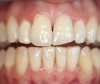

Figure 6  Multiple diastemas requiring closure to improve smile design.

Figure 6

Figure 7  Diastema closure with composite.

Figure 7

Figure 8  Full-face photograph of the ìbeforeî smile.

Figure 8

Figure 9  Full-face photograph of the smile following smile design and diastema closure.

Figure 9

In Case 3, diastemas between front teeth were closed with composite. The maxillary lateral incisors were increased in size to be proportionately correct to the central incisors. Completion required all 12 principles of composite restoration (Figure 6 through Figure 9).